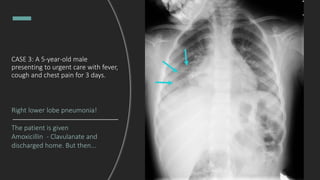

CASE 3: A 5-year-old male

presenting to urgent care with fever,

cough and chest pain for 3 days.

Right lower lobe pneumonia!

The patient is given

Amoxicillin - Clavulanate and

discharged home. But then...